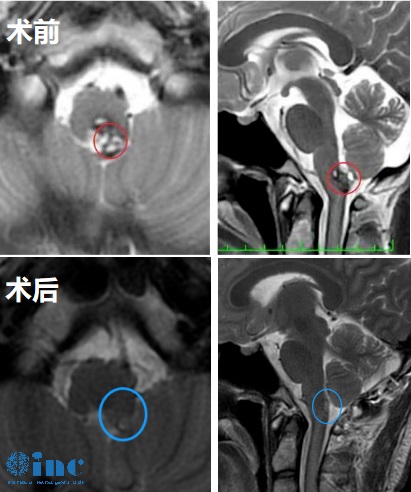

◉患者情况:今年4月,林先生由于偶尔头痛去医院进行头颅MRI检查,发现延髓及颈髓交接区病变。后续又进行强化MR检查,提示:延髓及颈髓交接区病变,结合病史,考虑脱髓鞘病变,大小约0.5*0.3*0.6cm。咨询各医院专家后,一致建议:目前肿瘤无占位效应,短期内复查,未给予任何治疗。虽然占位很小,但是林先生每天偶尔会有头晕、头痛,位置还不固定。5月进行复查MRI平扫+增强提示病变增大了。术后是可能插管过一生,还是现在止步于此?林先生不甘人生就这样了,多方咨询之后找到INC巴特朗菲教授。通过INC,林先生对身处德国的巴教授进行了邮件咨询,在巴教授的准确回复,让林先生瞬间充满信心。

◉治疗经过:林先生果断咨询了巴教授示范手术名额,手术成功,巴教授为这名高难度延髓肿瘤患者顺利全切,术后无任何新发神经损伤,术后一天意识清醒,四肢活动正常、言语呼吸吞咽功能正常。

◉术后情况:术后一天,巴教授团队偶遇前往术后核磁的林先生一家,对林先生进行了问候。术后一个多月,患者行走自如已基本恢复正常生活。